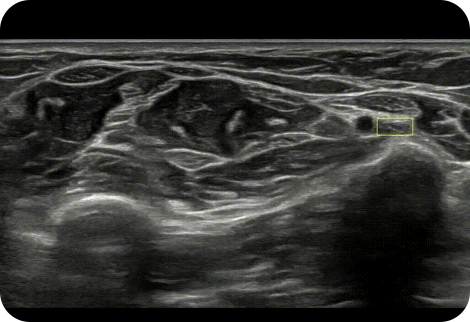

Display needle tip clearly

NeedleMate+™ ¹ delineates needle location when performing interventions such as nerve blocks. Improved accuracy and efficiency in procedure are possible with beam steering added to NeedleMate+™.

Detect and track nerves

with AI technology

NerveTrack™ ¹ is a function that detects and provides information of the location of the nerve area in real-time during ultrasound scanning.